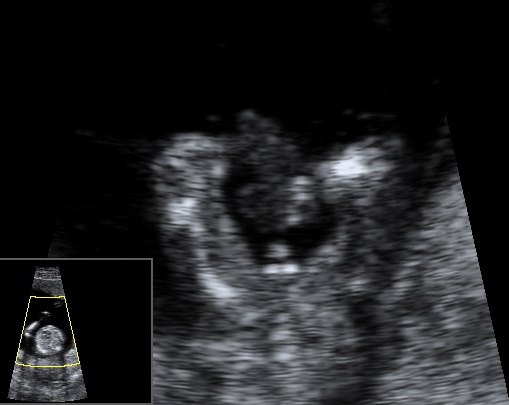

Det tror jeg på... Hehe... Sådan ser vores billeder fra kønsscanningen ihvertfald ikke ud fra uge 15 - og vi venter os en pige, så det er jo meget heldigt, at de ikke ligner hinanden